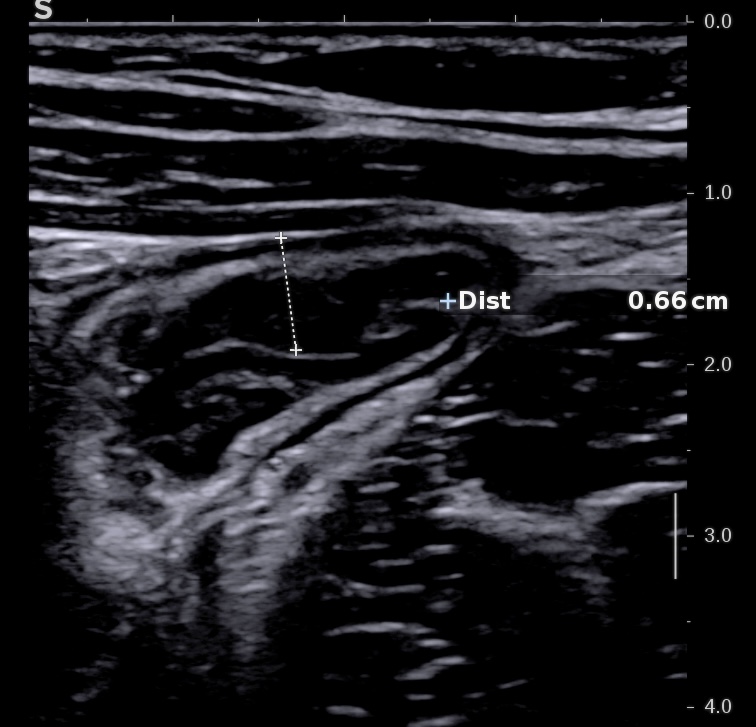

L'épaississement se mesure entre la muqueuse (hypoéchogène) et la musculeuse (hypoéchogène),

Ci dessous même portion avec et sans compression douce.

Il faut faire la moyenne de plusieurs mesures (≥3) en coupe longitudinale et transversale